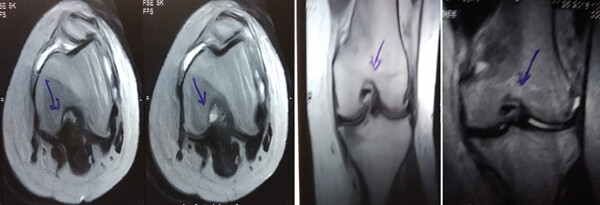

MRI:治療前后的MRI結(jié)果

治療前 MRI 顯示內(nèi)側(cè)和外側(cè)半月板后角 III 級撕裂。

治療后MRI檢查顯示內(nèi)側(cè)和外側(cè)半月板后角撕裂有所改善。患者癥狀改善,日常生活活動(dòng)能力增強(qiáng)。

結(jié)論:間充質(zhì)干細(xì)胞治療后,MRI檢查顯示內(nèi)側(cè)和外側(cè)半月板后角撕裂有所改善 ,關(guān)節(jié)功能也有改善,未出現(xiàn)嚴(yán)重不良事件。可以達(dá)到干細(xì)胞治療半月板損傷短期療效的目標(biāo)。